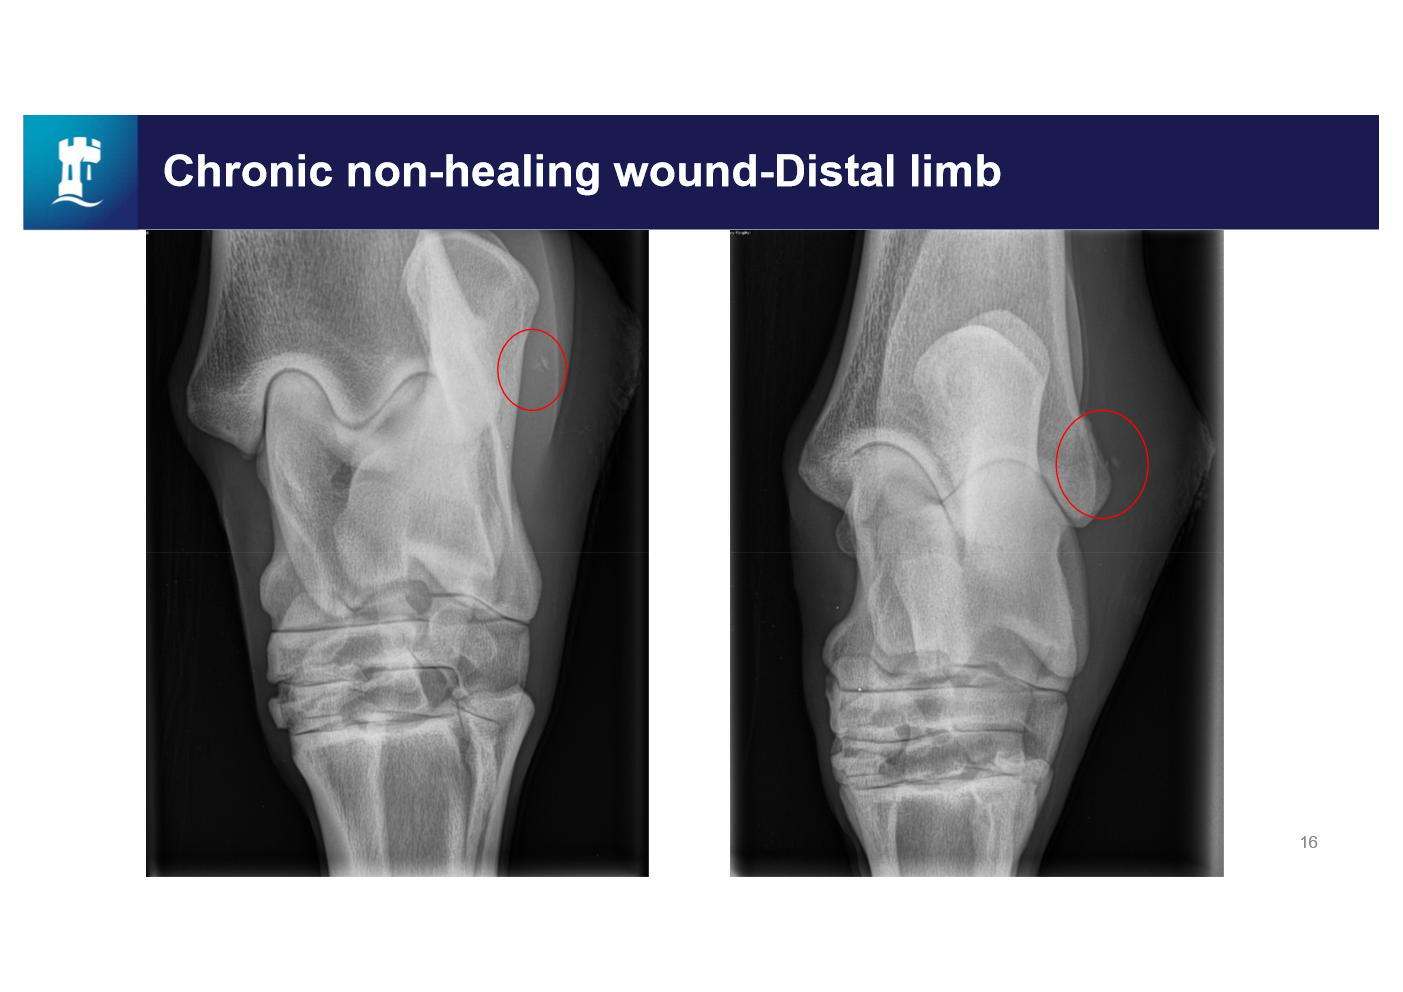

describe this wound

granulation tissue

epithelial tissue

sloughing

lots of movement

not good blood supply

not granulating over foreign body

infected

what is this main reason for the chronic non-healing wound

Periosteal elevation

Soft tissue swelling

bone fragment - acting as a foreign body

debride thoroughly

flush